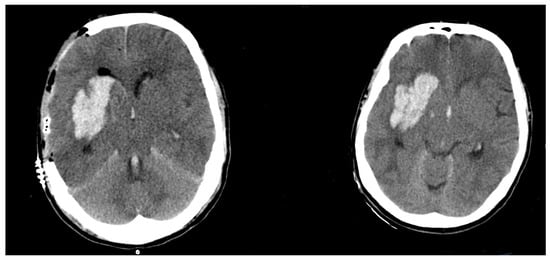

Postoperative Hematoma Expansion in Patients Undergoing Decompressive Hemicraniectomy for Spontaneous Intracerebral Hemorrhage

3.1. Preoperative/Postoperative Size Differences